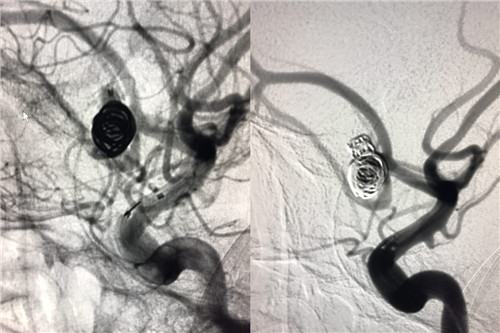

术中造影

患者赵某,8月28日因“蛛网膜下腔出血”入住我院神经外科。入院时意识呈浅昏迷,且意识障碍进行性加重伴随右侧瞳孔散大,曲友直教授团队根据颅脑CT判定患者为动脉瘤引起的蛛网膜下腔出血。由于动脉瘤在人体内像个定时炸弹,随时会再次破裂,危险性非常大。能否及时为患者实施动脉瘤手术,避免动脉瘤继续破裂,从源头遏制患者病情继续恶化的可能性,直接关系到患者的预后。曲教授团队制定了详细的诊疗计划,在最短时间内为患者行侧脑室外引流术,并及时为患者实施了全脑血管造影,结果证实了术前判断,是大脑前交通动脉瘤,分上下两叶、宽颈。考虑到患者脑肿胀明显,基础状态差,急诊行开颅夹闭手术风险极高,曲友直教授团队反复评估、综合考虑后为患者实施了双导管技术宽颈动脉栓塞术。实施双导管技术避免支架辅助对前交通宽颈动脉瘤进行栓塞,术后患者无须长期口服抗血小板及抗凝药物、为患者术后赢得了进一步康复的机会、减少了长期服药的经济负担。手术过程十分顺利,术后患者病情稳定,正在进一步恢复治疗中。